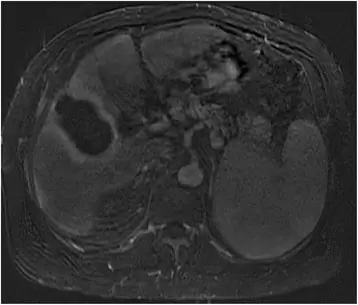

В дополнение к паттерну усиления были описаны дополнительные признаки ГЦК, которые также специфичны для ГЦК, включая капсульное усиление (30, 45, 46). Капсулярное усиление (рис. 2) определяется как постоянный периферический усиливающий ободок, наблюдаемый на венозной и отсроченной фазах.

фигура 2

Мужчина 67 лет с алкогольной болезнью печени и циррозом печени. МРТ венозной фазы с гадолинием демонстрирует узелок ГЦК на куполе печени с капсульным усилением

Изображение в полном размере